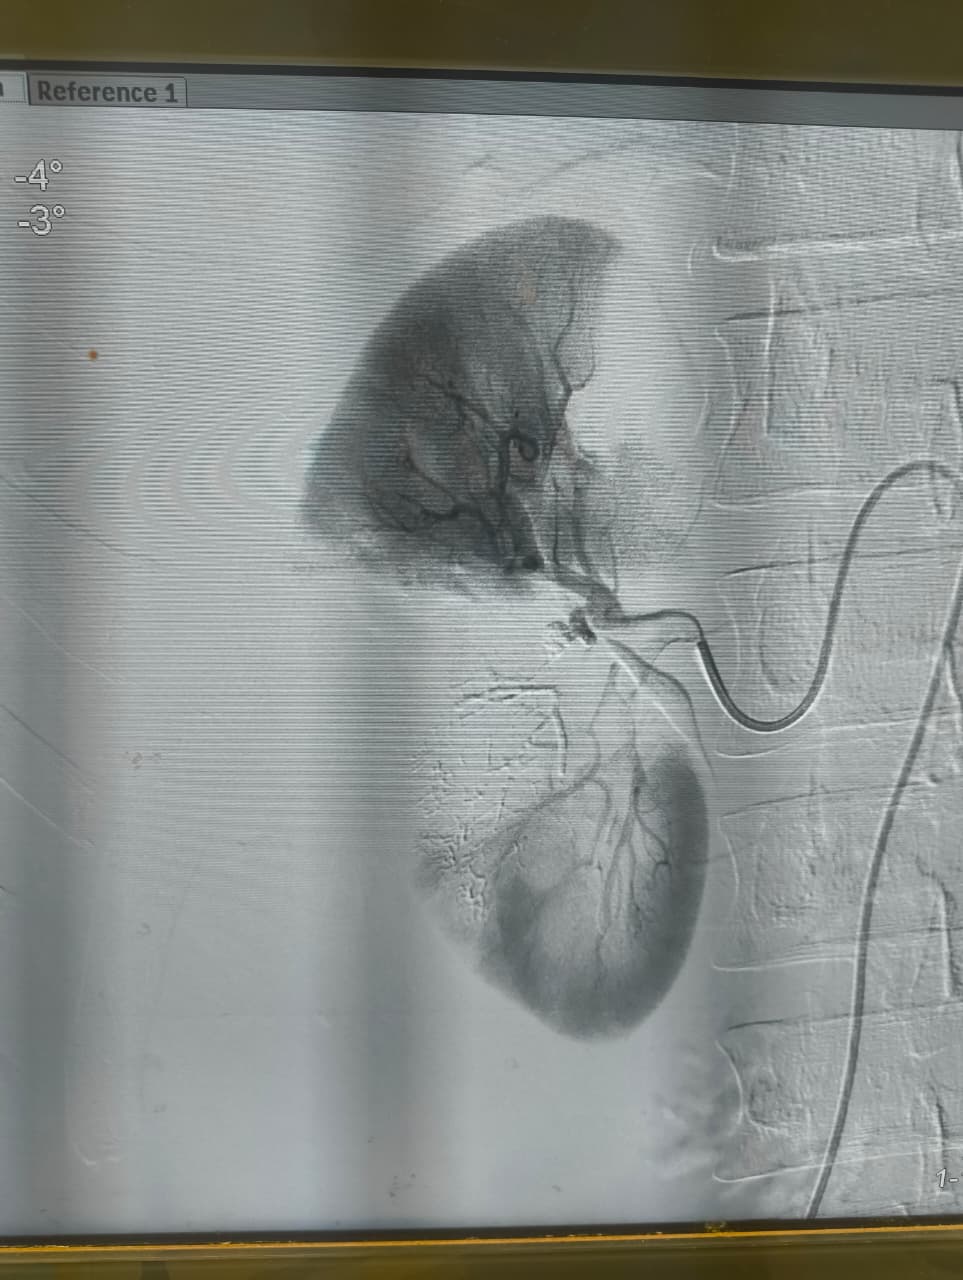

نجح الفريق الطبي بوحدة الأشعة التداخلية في إنقاذ شاب مصاب تعرّض لحادث أدى إلى قطع جزئي في الشريان الكلوي الأيمن مصحوبًا بتجمع دموي كبير خلف الغشاء البريتوني، وذلك دون اللجوء إلى استئصال الكُلى أو التدخل الجراحي التقليدي.

وتمكن فريق وحدة الأشعة التداخلية برئاسة الدكتور محمود غلاب، أستاذ الأشعة التداخلية بطب كفر الشيخ، من إجراء تدخل طارئ ناجح، تم خلاله سد التمدد الشرياني مع الحفاظ الكامل على التغذية الدموية لباقي أنسجة الكُلى، وهو ما يُعد من أبرز وأهم مميزات الأشعة التداخلية.

وقال الفريق الطبي، إن الأشعة التداخلية تتميز بقدرتها الفائقة على الوصول إلى أدق شرايين الجسم وإجراء تدخلات عالية الدقة والصعوبة دون أي تدخل جراحي، بل ودون الحاجة إلى التخدير الكلي.